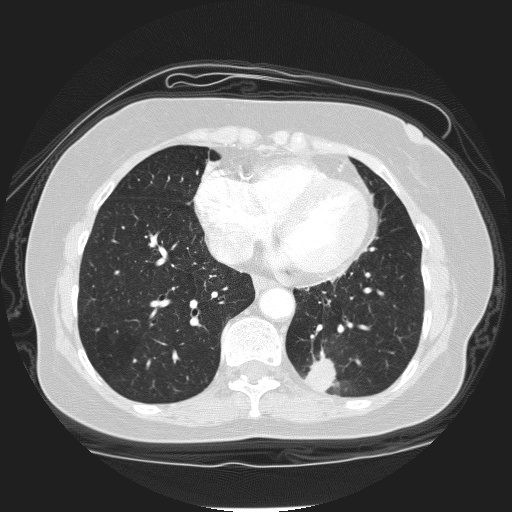

Table 1: Side-by-side comparison abnormal detection.

Sample 1: Abnormality detection Sample 2: Abnormality detection

Question: Does this image look abnormal?

Answer: <think> Yes, the image appears abnormal due to the presence of irregularities in the lung fields and potential signs of pathology. The overall lung structure may show unusual densities or patterns that deviate from normal anatomical features. These findings could indicate conditions such as infection, inflammation, or other pulmonary issues that warrant further investigation </think> <answer> yes </answer>.

Short answer: Yes.

[Uncaptioned image]

Question: Is the lung healthy?

Explainable Answer: <think> The lung appears to show signs of pathology, indicated by the presence of abnormal structures and potential lesions. These findings suggest that the lung is not functioning optimally and may be affected by a disease process. Further evaluation and clinical correlation are necessary to determine the specific condition affecting the lung. Overall, the imaging suggests that the lung is not healthy </think> <answer> no </answer>.

Short answer: No.